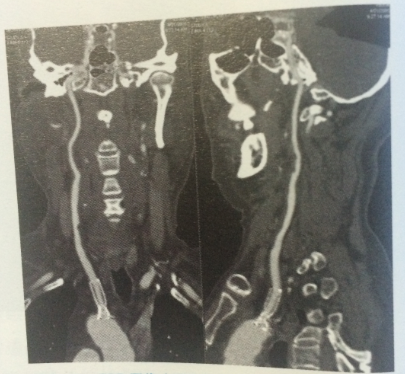

CPR是在一个维度上选择特定的曲线路径,将该路径上的所有体素在同一平面上进行显示,可以一次评价曲度较大的结构如脾动脉、胰管、冠状动脉等管状结构的全长情况,例如图一头颈血管显示。